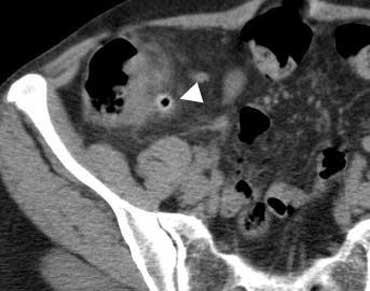

Sỏi tiết niệu

Sỏi tiết niệu thường gây đau hông lưng, nhưng sỏi niệu quản (đầu mũi tên) đôi khi có thể biểu hiện với các dấu hiệu lâm sàng bắt chước viêm ruột thừa, viêm túi mật hoặc viêm túi thừa.

Ngược lại, viêm ruột thừa có thể gây tiểu máu, tiểu mủ và tiểu đạm ở tới 25% bệnh nhân do viêm niệu quản từ ruột thừa viêm lân cận.